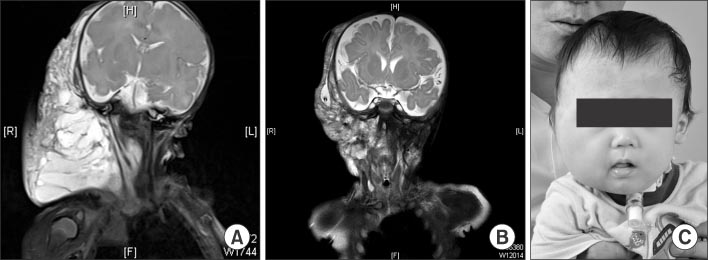

Fig. 3

(A) Patient No. 6 visited our hospital after having gotten several times of sclerotherapies using OK-432 and ethanol. (B) This photograph was taken 3 years after surgery.

Fig. 3 (A) Patient No. 6 visited our hospital after having gotten several times of sclerotherapies using OK-432 and ethanol. (B) This photograph was taken 3 years after surgery.